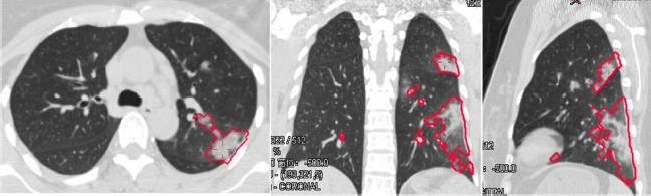

新型冠状病毒肺炎的病变检测

女,36,新型冠状病毒肺炎。横切位,计算机辅助检测发现左肺上叶有磨玻璃阴影和实变(图 A);冠状位,计算机辅助检测发现左肺上叶、下叶、胸膜下均有磨玻璃阴影和实变(图 B);矢状位,作为上叶斜裂下、下叶后段有磨玻璃阴影和实变(图 C)。从分割效果上看,计算机辅助发现病变与影像学所见基本一致。